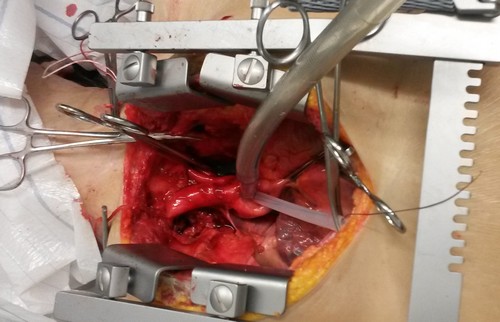

| Am

12.11. 2014 testete das Ulmer Kompetenzteam in Gegenwart von Michael

Wagner (DGAB-Vorsitzender) und Karen Conrad - welche im medizinischen

Bereich arbeitet - eine auf das Gehirn zentrierte Perfusionsmethode

mit auf 0°C gekühlter 75%iger

Vitrifikationslösung VM1 am Körper

eines vor etwa 24 Stunden Verstorbenen, der sich der medizinischen

Wissenschaft vermacht hatte. Solche Versuche sind interessant für die Testung von gerinnungs- hemmenden Mitteln und des postmortalen Verschlusses von Gefäßen, sowie die Erhaltung von überlebenden Zellen u.a. für die Alzheimer Forschung. Die Perfusion wurde nach medianer Sternotomie sowie Eröffnung und Spreizung des Thorax über eine arterielle Kanüle in der aufsteigenden Aorta und eine venöse Kanüle in der Vena cava superior als extrakorporaler Kreislauf angelegt. Durch Unterbindung der Armarterien beiderseits und Abklemmen der Bauchaorta wurde die Lösung über den Kopf geleitet. Der Kreislauf wurde von einer Rollerpumpe betrieben. Das System lief regelrecht, jedoch konnte der Rückfluss aus der oberen Hohlvene nur durch einen Wasserstrahlbetriebenen Sog erreicht werden. Ein Fluss im geschlossenen Kreislauf wurde aufgegeben, da sich so lange nach dem Ableben sehr viele Gerinnsel in der Lösung befanden. Frau Conrad schlug vor, zu versuchen ob Heparin entgegen der Theorie den Abgang der Thromben steigert (es werden immer wieder Erfahrungen in dieser Richtung diskutiert). Es wurden 35000 IE Heparin eingeführt. Es bestand der Eindruck, dass der Rückfluss sich dadurch etwas besserte. Wie zu erwarten trat eine pralle Konsistenz an Gesichtshaut und Hinterkopf auf, welche die selektive Kopf Perfusion bestätigte. Nach Entfernung der Klemmen und Kanülen wurde der Thorax verdrahtet und die Hautwunde geschlossen. Der Versuch dauerte drei Stunden. |

| Das Brustbein wurde eröffnet und gespreizt. Man sieht auf den Herzbeutel, der von etwas Bindegewebe bedeckt ist. |